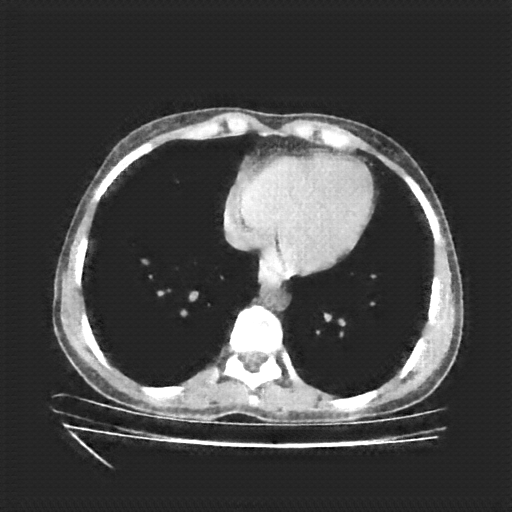

Original NATIVE CT scan (input)

Full window (WL 1023.5, WW 4095 β†’ Low βˆ’1024, High +3071)

Actual HU range: [-160.0, 240.0]

Mediastinum window (WL 40, WW 400 β†’ Low βˆ’160, High +240)